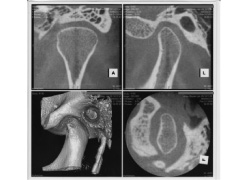

当院では初診時の検査で、ほとんどの患者さんで術者が複数のかみ合わせの記録を取って、それを使って咬合器に歯列模型を装着して、患者さん本来の正しい咬み合わせの位置と患者さんが自然と咬み合わせた位置の差を目に見える形で明らかにして診断を行っていきます。顎関節症が進行した方では顎関節部のCT撮影やMRI撮影を提携医療機関にて撮影していただき、その状態を把握することも行っています。単に歯並びを治したいだけなのにCT撮影やMRI撮影を行うのは大袈裟に感じるかもしれませんが、会話や咀嚼などの口腔の機能を正しく行うために顎関節はその要になる部位であり、その状態をできるだけ詳細に知ったうえで診断を行い、治療計画に反映させることが大切だからです。歯並びや咬み合わせの改善だけでなく、顔貌の改善や歯の周囲の歯肉や骨を健康に保つためにも顎関節の状態は軽視できません。

検査でずれが大きい方、すでに顎関節症の症状のある方はCT検査、MRI検査を撮影していただき顎関節内部の状態を精査します。